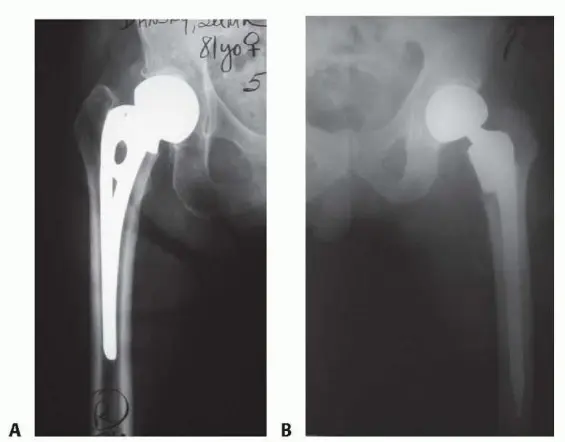

النوع أحادي القطب (Unipolar type):

مثل مفصل أوستن مور (Austin Moore). في هذا النوع، يتكون رأس الفخذ الاصطناعي من قطعة واحدة تتحرك مباشرة داخل التجويف الحقي الطبيعي.

- الشكل 1 أ: مفصل أوستن مور الاصطناعي.

النوع ثنائي القطب (Bipolar type):

يتكون هذا النوع من رأس داخلي صغير يدور داخل غلاف معدني أكبر، والذي بدوره يدور داخل التجويف الحقي. يُفضل هذا النوع نظريًا لأنه يقلل من الاحتكاك والتآكل على جانب التجويف الحقي، حيث أن الحركة تتوزع بين الرأس الداخلي والغلاف الخارجي، مما يؤدي إلى حركة أقل عند واجهة التجويف الحقي-الغرسة.

- الشكل 1 ب: مفصل ثنائي القطب مثبت بالإسمنت.